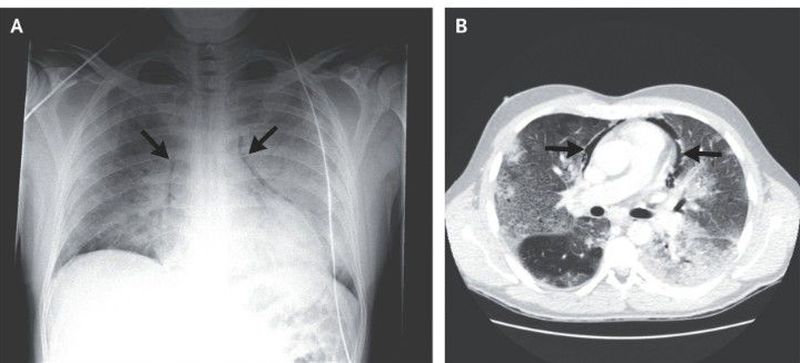

A previously healthy 33-year-old man presented to the emergency department with a 10-day history of lethargy and feeling unwell. His temperature was 38.3°C, and he had tachycardia, with an oxygen saturation of 85% while breathing 15 liters of oxygen per minute through a nonrebreather mask. The physical examination was notable for bronchial breath sounds in the left lower lung; no subcutaneous emphysema was palpated. Chest radiography showed perihilar opacities in both lungs with free air in the mediastinum (Panel A, arrows). Computed tomography confirmed pneumomediastinum (Panel B, arrows) with enhanced interstitial markings and lower-lobe opacities in both lungs, with greater severity in the left lung. The throat swab was positive for influenza A (H1N1). The patient received noninvasive ventilatory support and was treated with zanamivir for influenza and piperacillin–tazobactam for bacterial superinfection. The pneumomediastinum resolved without additional intervention, and the patient was discharged from the hospital 15 days after presentation.